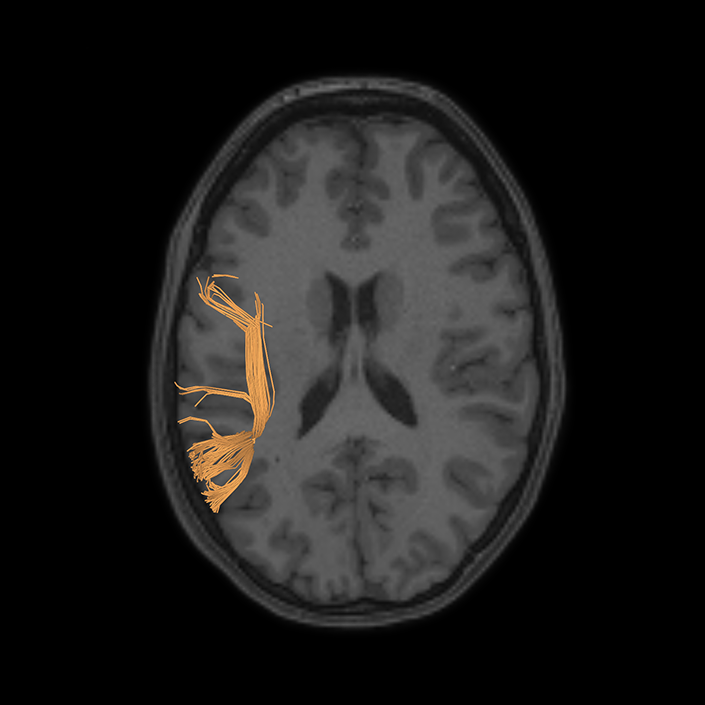

ᐅ SummaryArea 44: part of the inferior frontal gyrus of the lateral frontal lobe. Translates abstract and intentional information in the prefrontal cortex to more detailed representations to help guide the production of verbal and manual actions. In addition to its known association with Broca's area, is sometimes represented as part of Broca's complex ᐅ Where is it?Area 44 is at the posterior most part of the inferior frontal gyrus. It is the anterior bank of pars opercularis of the IFG. ᐅ What are its borders?Area 44 borders area 45 anteriorly and area 6r posteriorly. Area 8C is its medial border and its inferior border is wedged between then upper borders of Areas 6R and 6V. Its superior edge borders IFSp and IFJa. Its opercular surface is FOP4. ᐅ What are its functional connections?Area 44 demonstrates functional connectivity to areas SFL, IFSp, IFJa, 45, 47s, 47L, 9a, 9m, 8AV, 8BL and 8C in the dorsolateral frontal lobe, area 8BM in the medial frontal lobe, area 55b in the premotor areas, areas FOP5, AVI and PSL in the insula- opercular region, areas TGd, STSdp and STSvp in the temporal lobe, areas PFm, and PGi in the inferior parietal lobe, and no areas in the medial parietal lobe. ᐅ What are its white matter connections?Area 44 is structurally connected to the arcuate/SLF and the FAT. Connections with the arcuate/SLF project posteriorly and wrap around the Sylvian fissure to the middle temporal gyrus to end at TE1a and TE1m. There are also projections from the arcuate/SLF before it terminates to parcellations A5 and STSdp. The majority of the inferior connections of the frontal aslant tract end at 44, the tract is connected superiorly to superior frontal gyrus parcellations SFL, 6ma and s6-8. Local short association bundles are connected with 45 and 8C. White matter tracts from 44 in the right hemisphere have less consistent connections with the arcuate/SLF. ᐅ What is known about its function?Area 44 translates abstract and intentional information in the prefrontal cortex to more detailed representations to help guide the production of verbal and manual actions. Area 44, in addition to its known association with Broca's area, is sometimes represented as part of "Broca's complex", including Brodmann Areas 45, 46, 47 and the mesial supplementary motor area of 6, which contribute to a frontal-subcortical circuit. The right pars opercularis has also been implicated in cognitive inhibition in the overall context of working memory. |

DTI image |